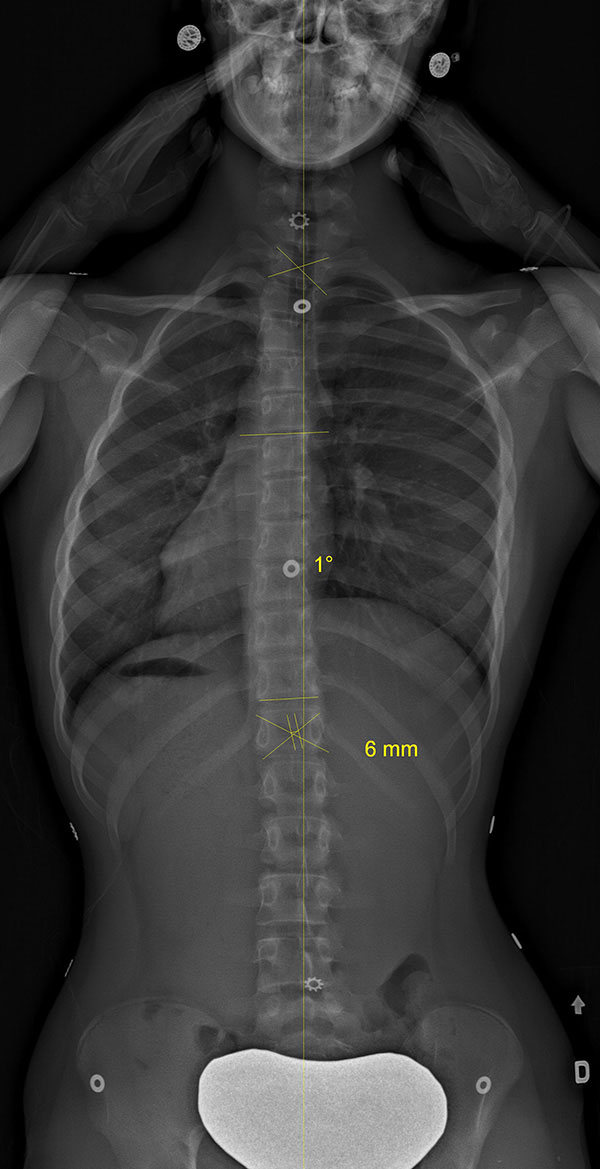

Adolescente scoliotique avant et après SpineCor®

Colonne vertébrale scoliotique d’une adolescente, avant le traitement SpineCor® et à la fin du sevrage après trois ans de port quotidien. Les radiographies démontrent une correction spectaculaire.

Colonne vertébrale de l'adolescente avant SpineCor® |

Colonne vertébrale de l'adolescente avec SpineCor® |